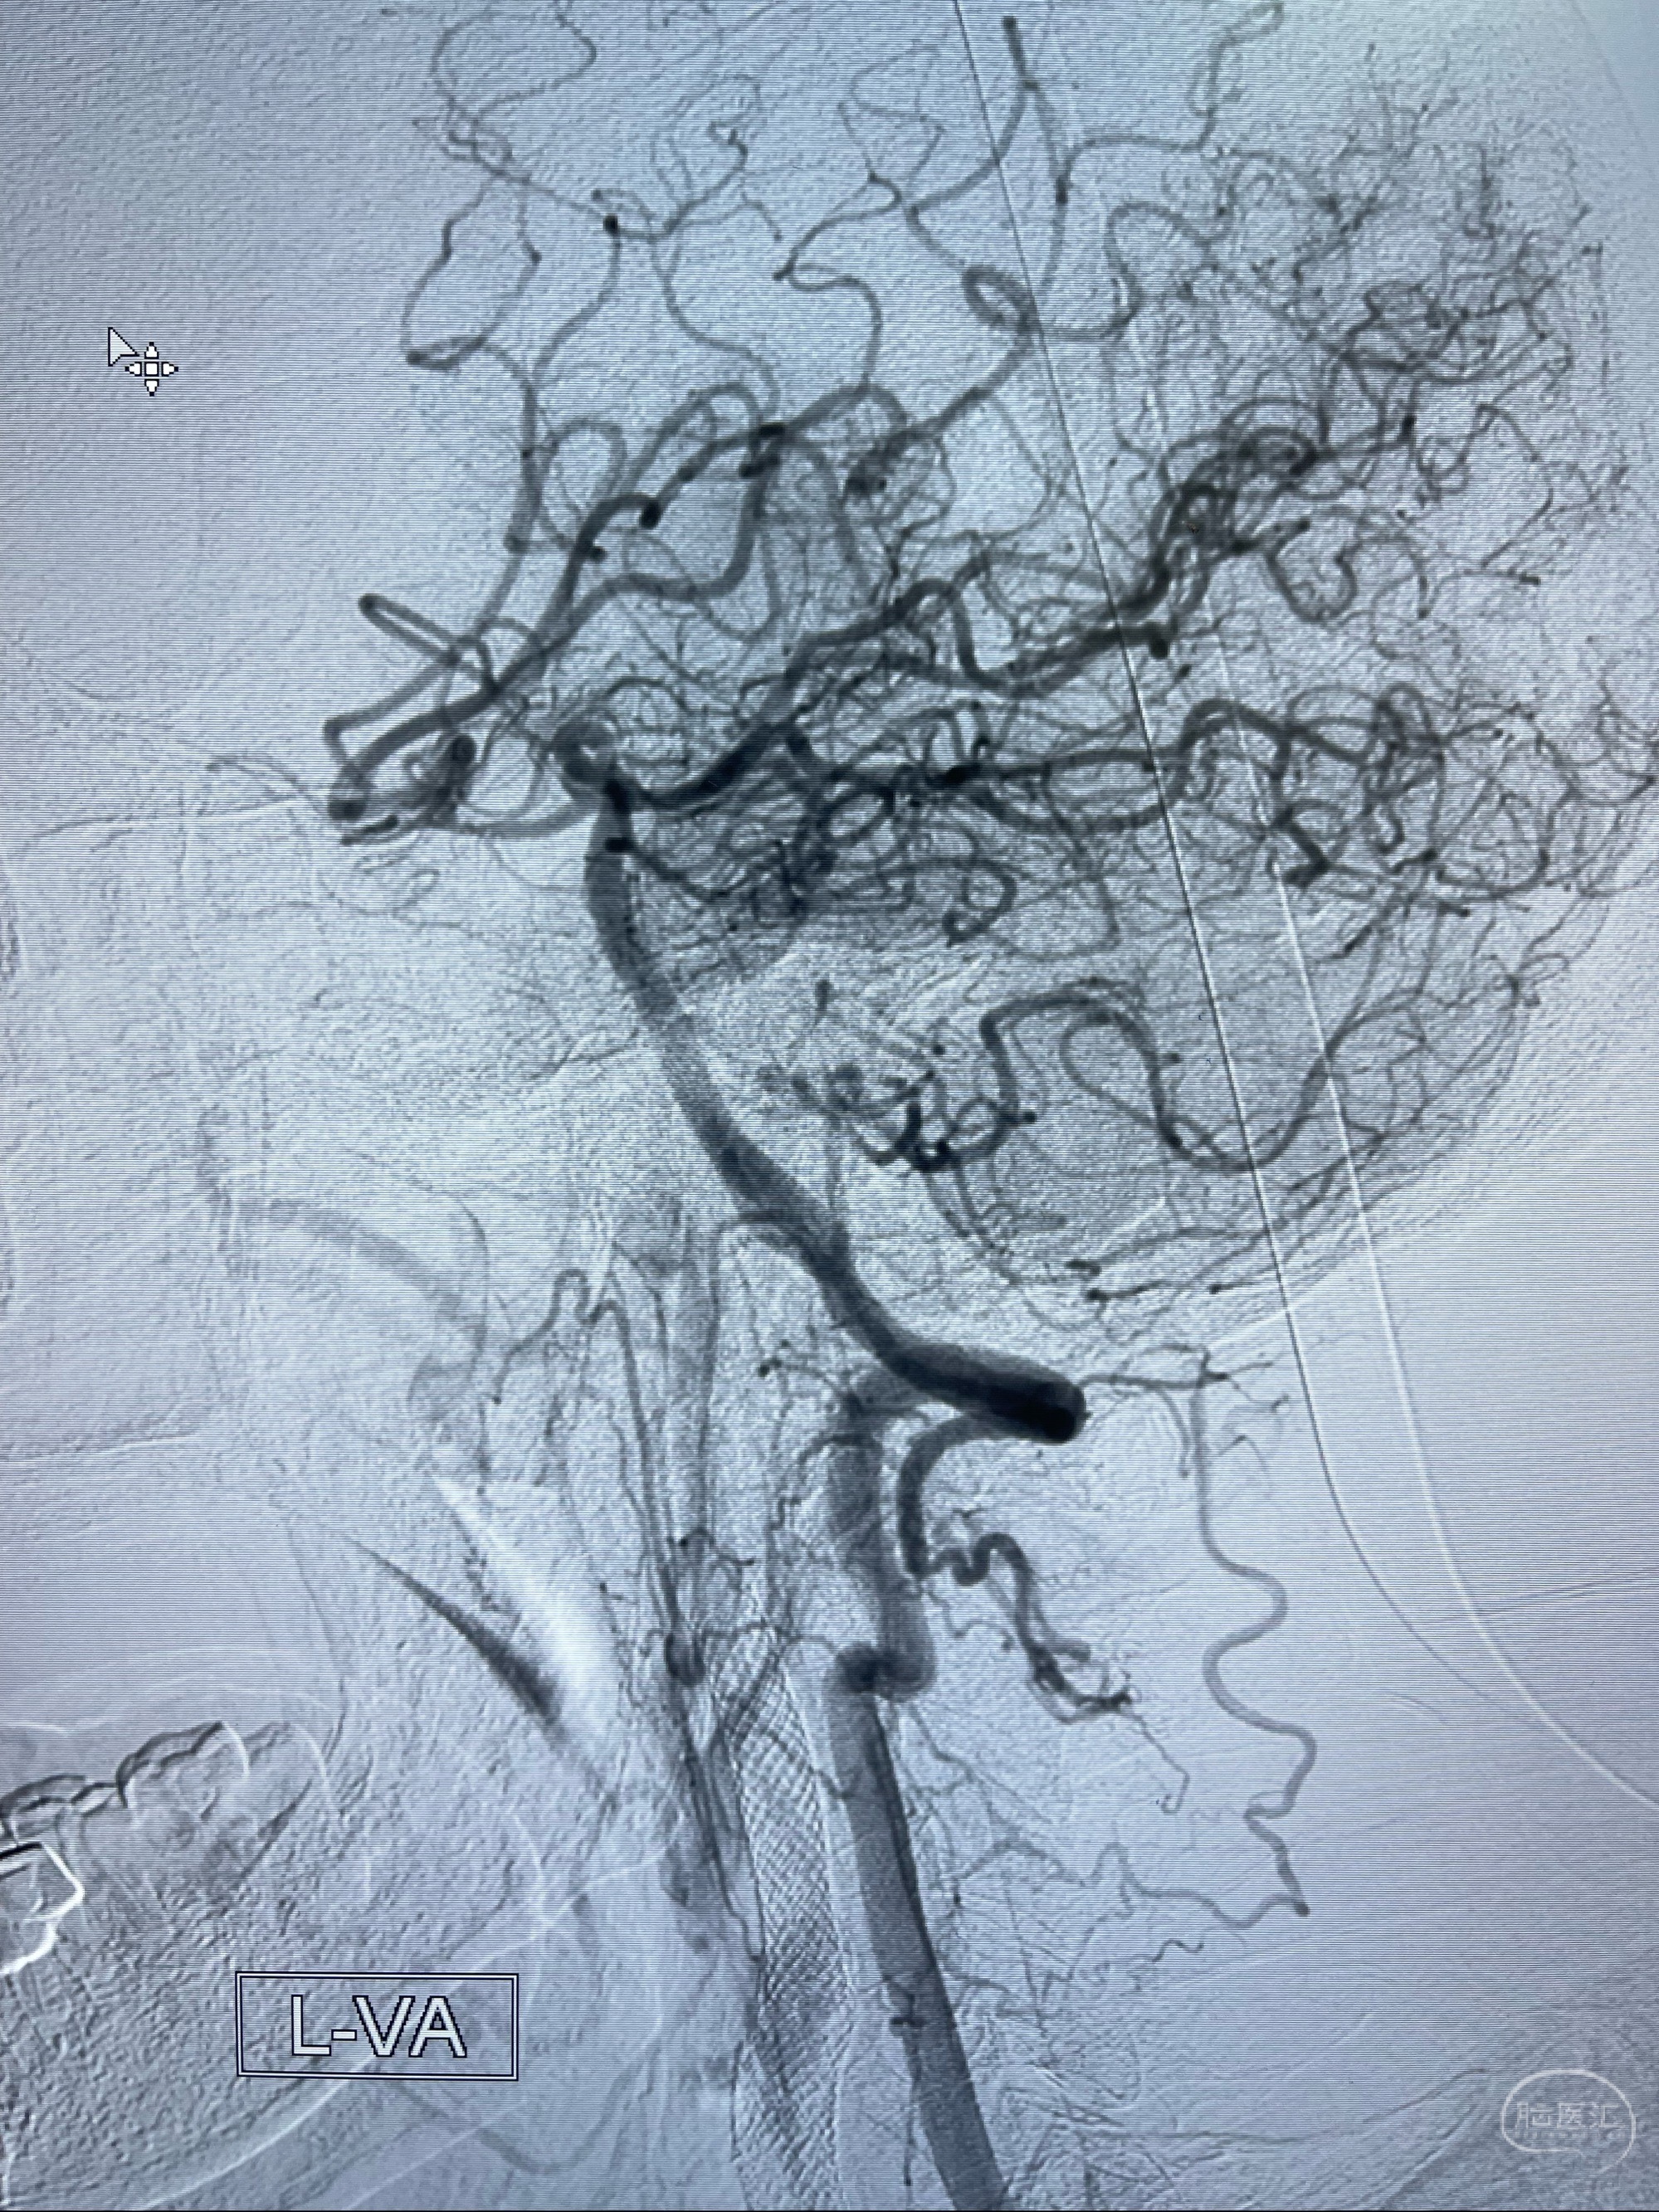

2023-07-10DSA:右侧颈内动脉岩骨段夹层伴中偏重度狭窄改变,左侧颈总动脉闭塞、右侧颈外动脉由右侧肋颈干甲颈干吻合代偿

左侧椎动脉可见代偿显示左侧前循环